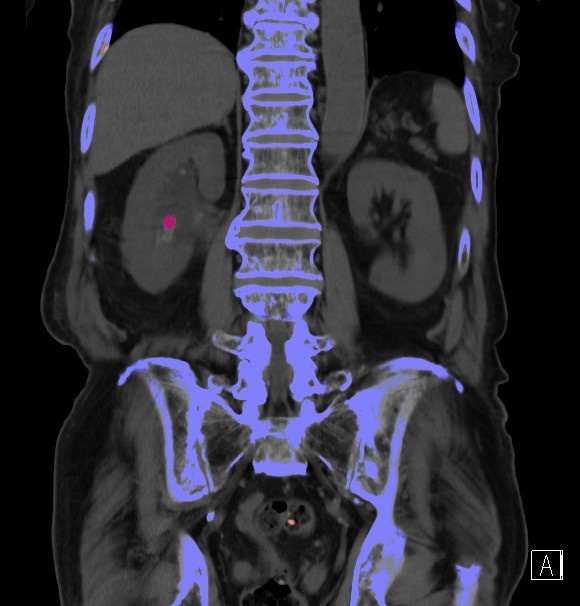

腹部領域

腎結石の成分評価が可能

【腎結石】

腎結石は、結石の主成分によって治療方針が異なります。これまでは結石の有無、形状評価は可能でしたが成分までは判断することは不可能でした。

しかし、Dual Energyイメージングで撮影することで結石に成分評価が可能となり、その後の治療方針判断に使用することができます。